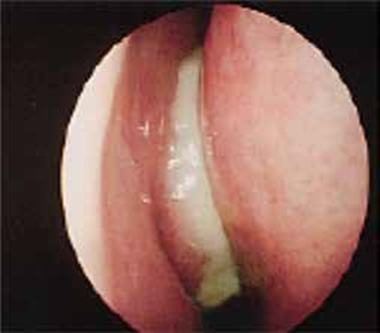

L’échographie abdominale réalisée objectivait une vésicule à paroi fine siège de plusieurs mini-calculs (Figures 1, 2).

Une cœlioscopie réalisée a montré de multiples granulations blanchâtres disséminées dans la totalité du foie, le reste de l’exploration était sans particularité (Figures 6 ,7). Une cholé-cystectomie associée à une biopsie hépatique objectivant une granulation blanchâtre, ont été réalisées.